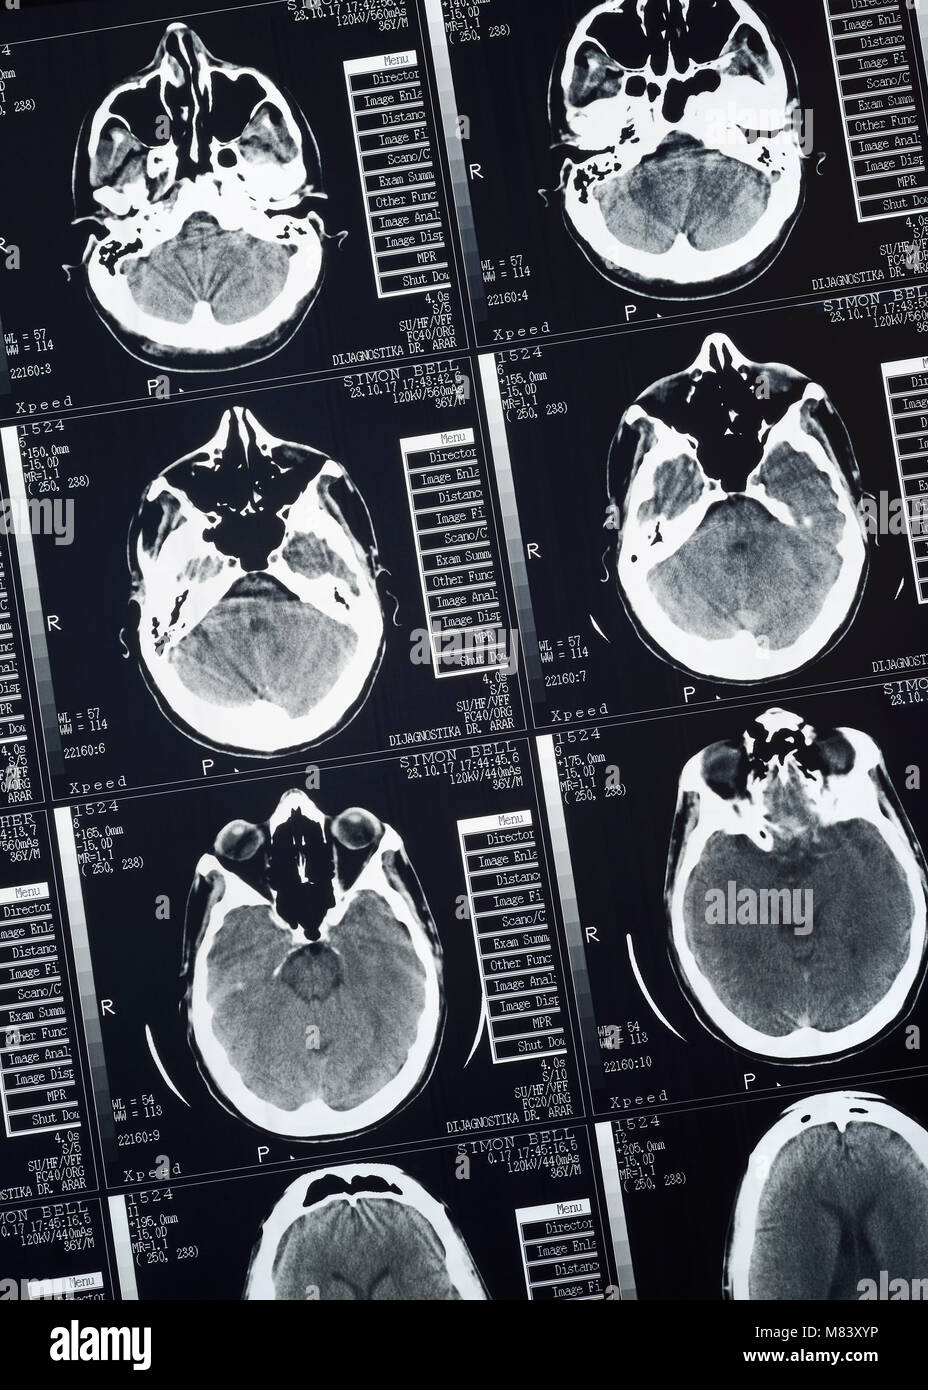

CT Scan d'un mâle humain Cerveau, Close Up Banque D'Imageshttps://www.alamyimages.fr/image-license-details/?v=1https://www.alamyimages.fr/photo-image-ct-scan-d-un-male-humain-cerveau-close-up-177107946.html

CT Scan d'un mâle humain Cerveau, Close Up Banque D'Imageshttps://www.alamyimages.fr/image-license-details/?v=1https://www.alamyimages.fr/photo-image-ct-scan-d-un-male-humain-cerveau-close-up-177107946.htmlRMM83XYP–CT Scan d'un mâle humain Cerveau, Close Up